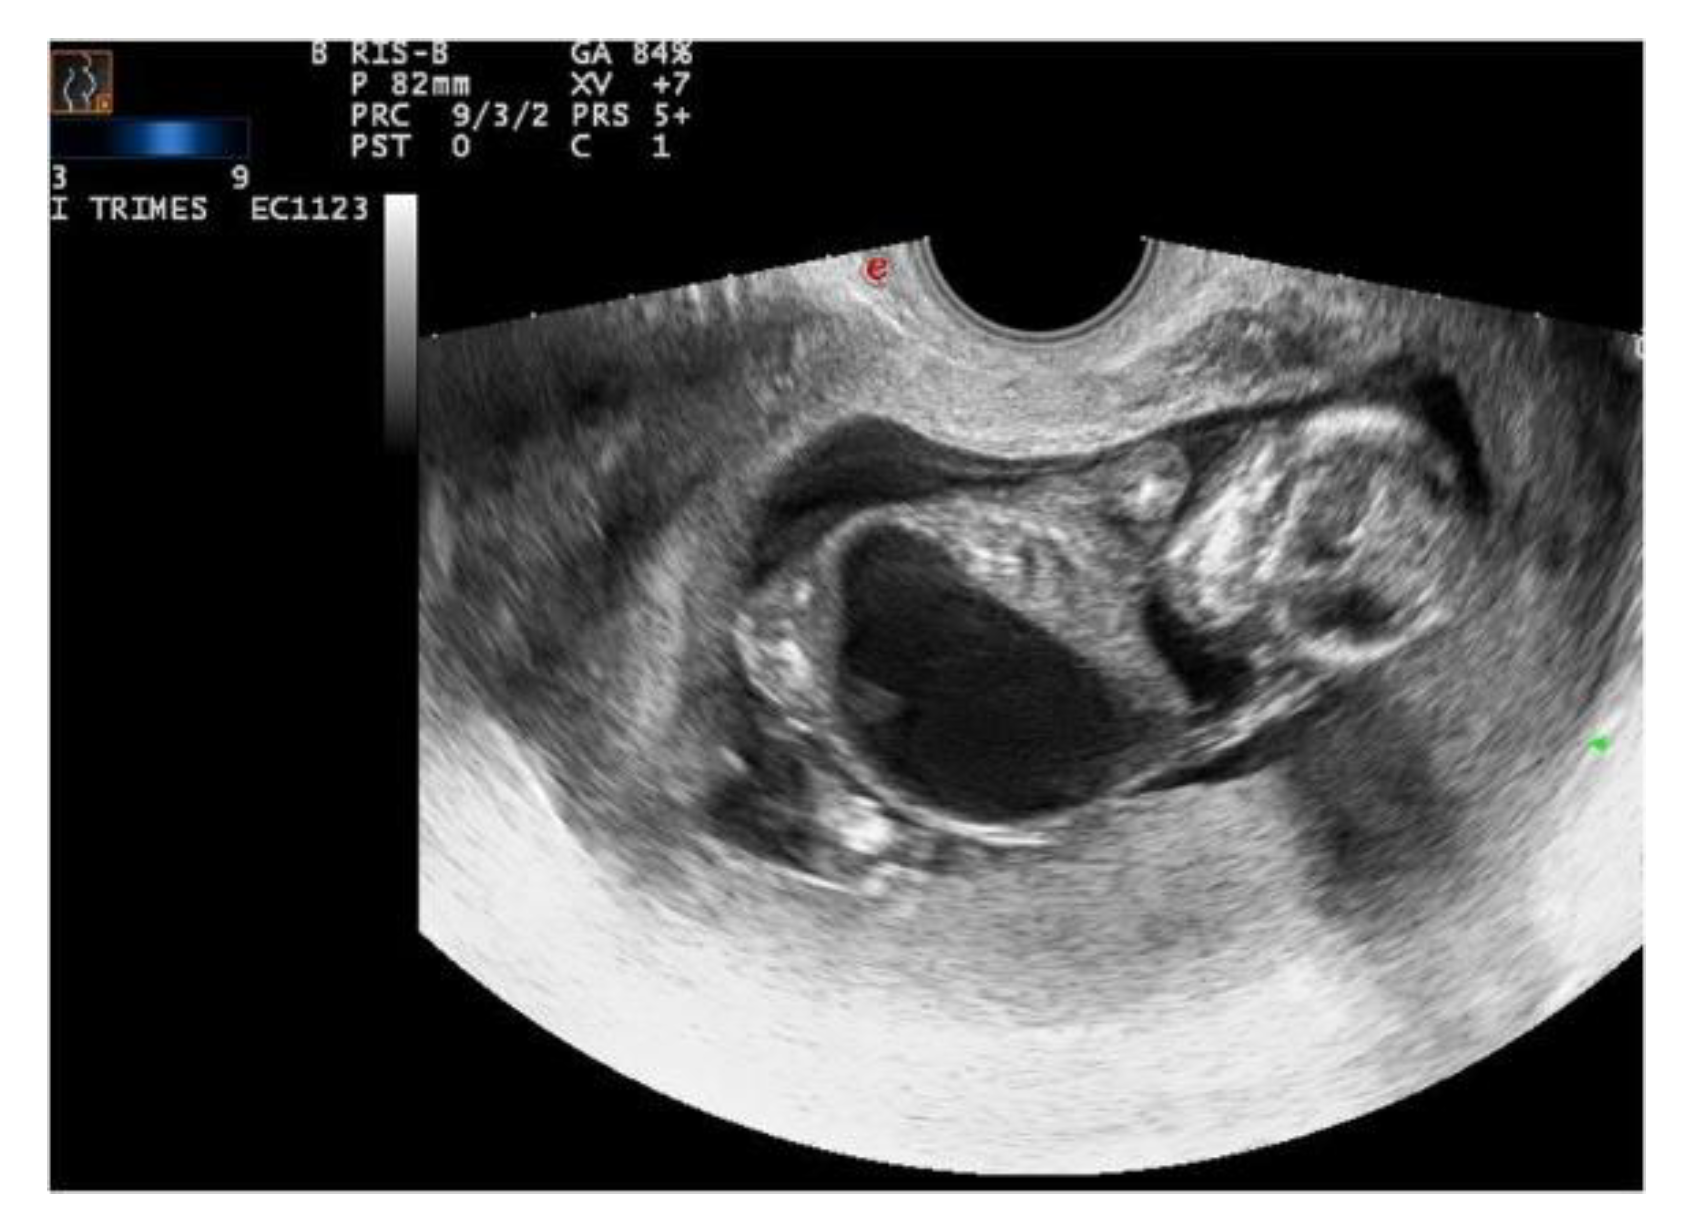

Ecographic diagnosis: urinary obstruction syndrome due to posterior urethral valve (PUV). The US (ultrasonographic) examination showed a megacystis with a maximum diameter of 44 mm and mild hydroureteronephrosis with bright hyperechogenic kidneys. The bladder had the so-called “key hole sign”, suggesting a possible PUV. Fetal biometry and amniotic fluid were appropriate for gestational age (GA). No other major abnormalities were detected (Figure 1).

Ecographic diagnosis: Prune-Belly syndrome, PBS. The ultrasonographic (US) examination was very difficult due to maternal BMI > 35 and the anhydramnios—absence of amniotic fluid. The fetus showed a megacystis with a maximum diameter of 38 mm. The whole fetal body had a very uncommon posture and it was impossible to assess other fetal structures because of the anhydramnios (Figure 2).

Figure 2. Case 2, US. Megacystis and anhydramnios. Courtesy of Dr. G. Giunta.